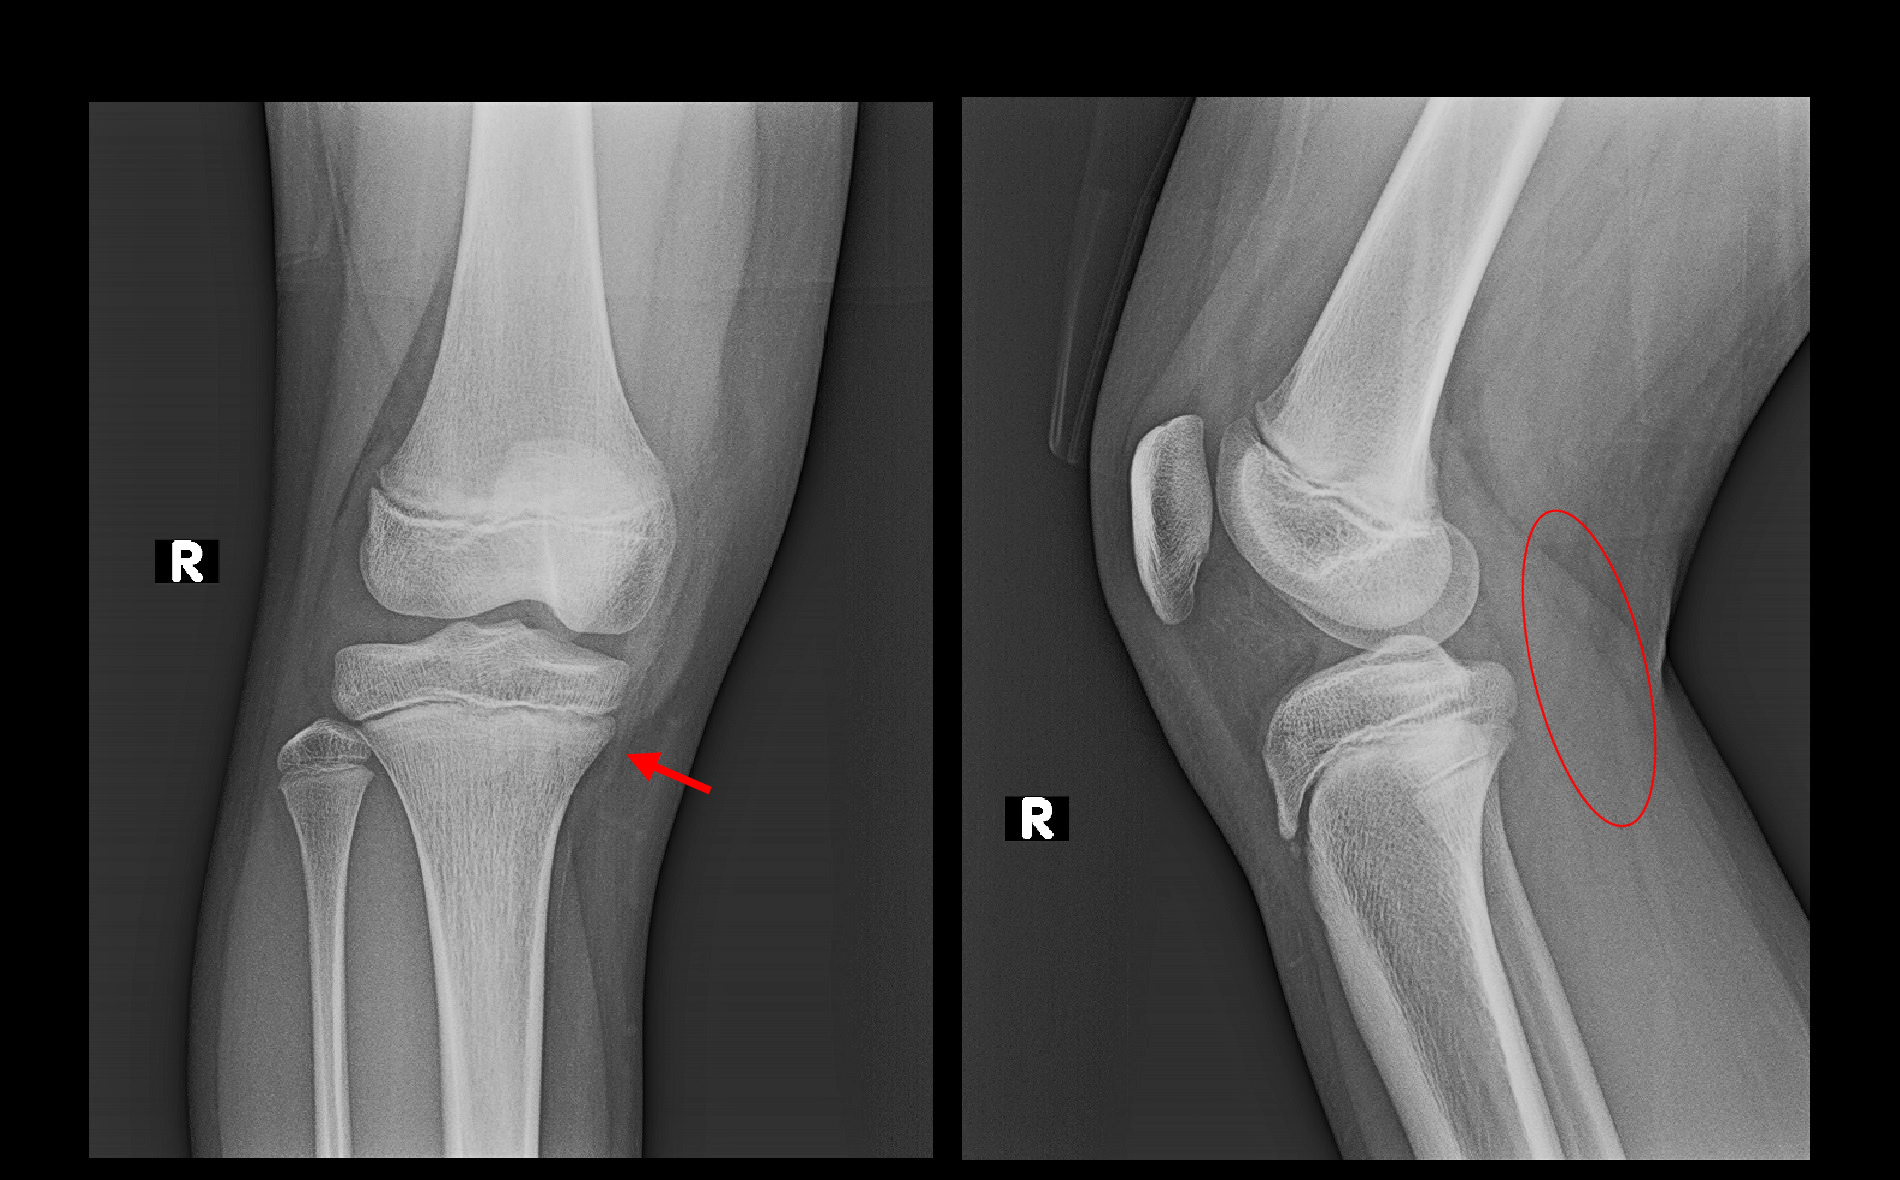

10才女 Xp.jpg

この子も右脛骨内顆部(赤矢印)に圧痛を認めました。7月の右足の舟状骨の疲労骨折の経過があるので、右膝も疲労骨折を疑いました。